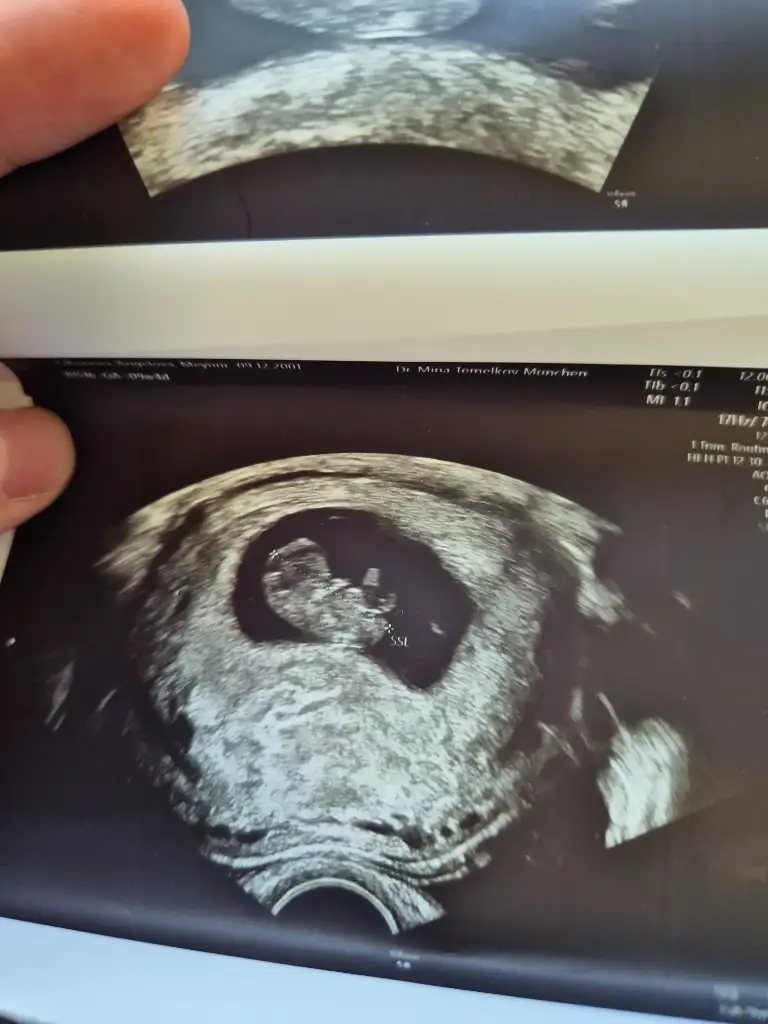

Kızlar 9haftalık gebelik sizce cinsiyet nedir?

Eklentiler

• 1000010842.webp

1000010842.webp

32,2 KB · Görüntüleme: 172

• 1000010843.webp

1000010843.webp

29,2 KB · Görüntüleme: 155